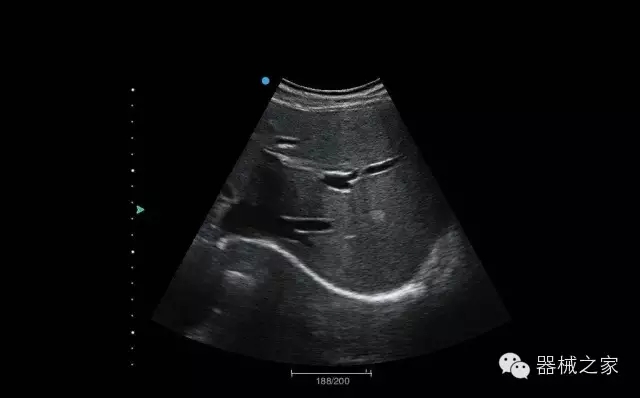

臨床圖片賞析

結(jié)甲

腎臟血流

肝血管瘤